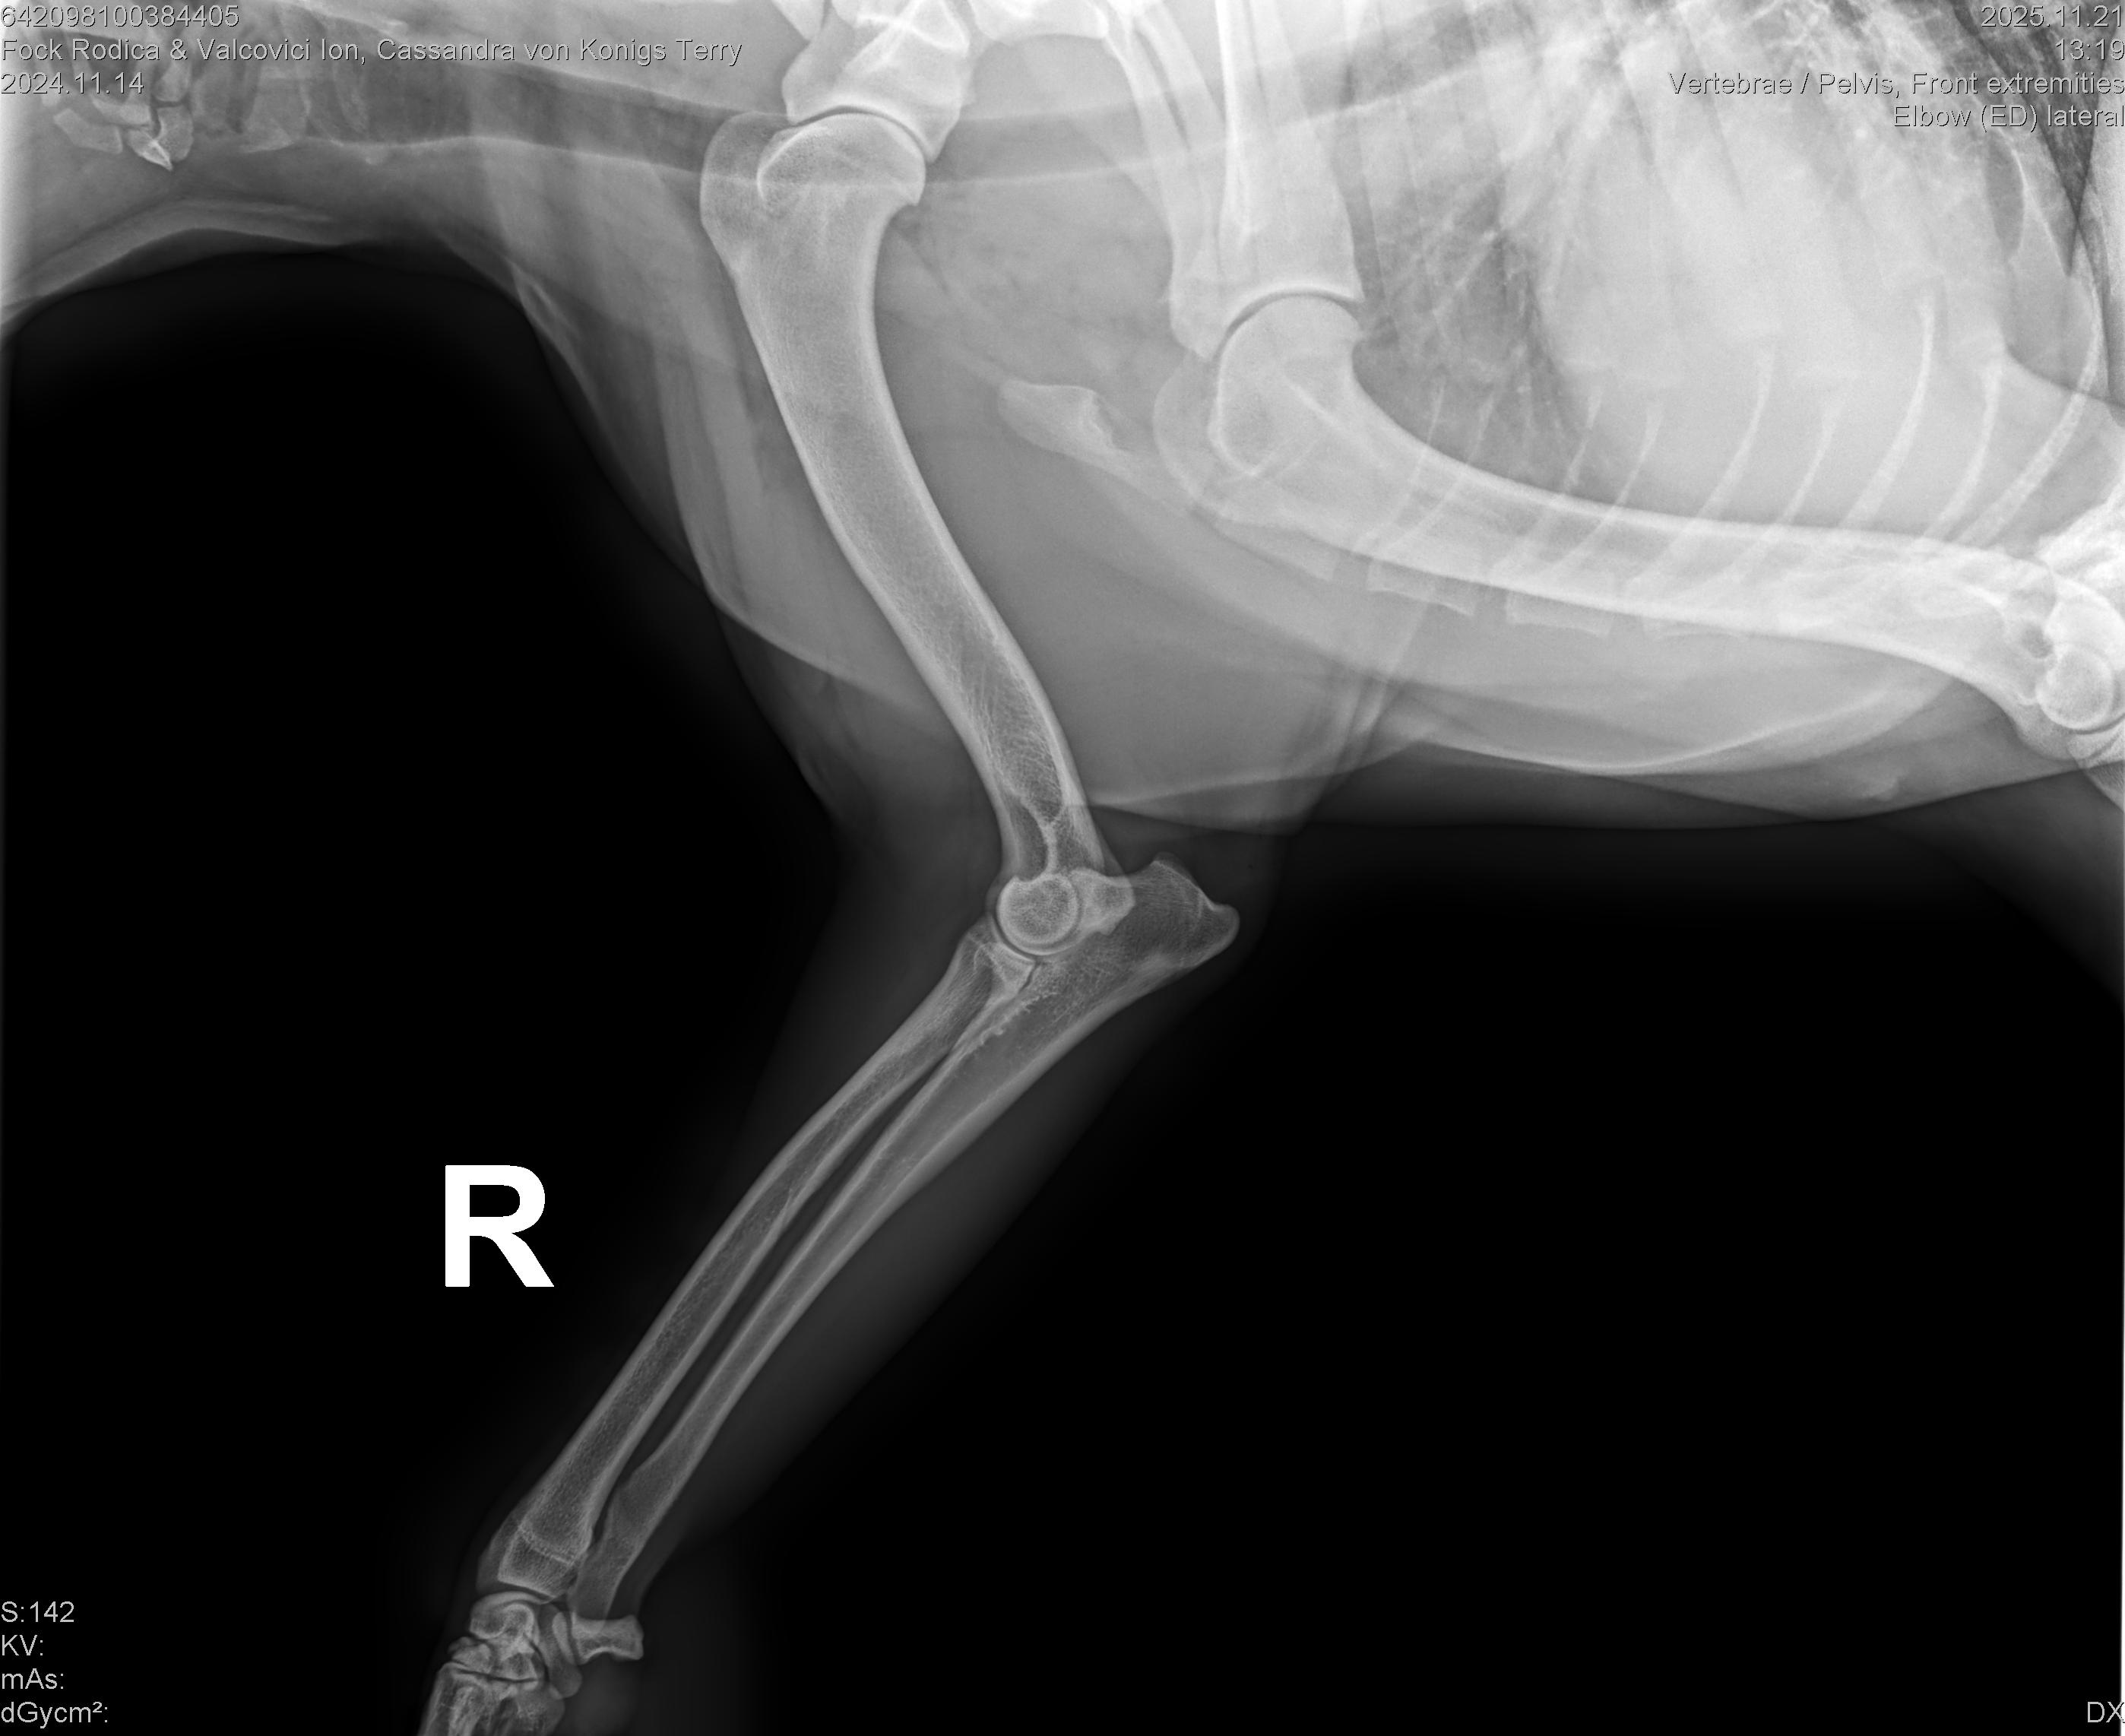

CASSANDRA VON KONIGS-TERRY

( CASSY )

Data nasterii:

14.11.2024

Crescator:

FOCK RODICA si VALCOVICI ION